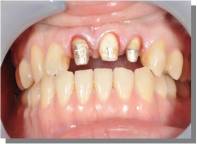

在口腔摄影里,因为拍摄环境的不同,所以需要黑板来增加摄影的成功率。黑色的物体可以吸收多余的干扰光,不仅能使主体颜色更加鲜明正确,还能与主体形成强烈的对比关系。

干货集结:

快门 1/125 、 光圈 F25 、 ISO 100

拍摄主体面向光源,不可多反光

比色板与牙齿保持于同一水平线